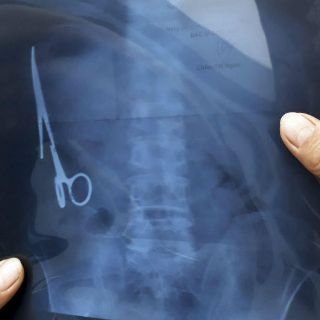

Radiografía tomadas tras accidente de tráfico revelaron la presencia del instrumento

BANGKOK, TAILANDIA (03/ENE/2016).- Un vietnamita ha vivido 18 años con unas tijeras que los médicos se olvidaron en su estómago y de cuya presencia nadie se había dado cuenta hasta el mes pasado, cuando sufrió un accidente de tráfico y le hicieron una radiografía.

La intervención quirúrgica para retirar el instrumento médico de 15 centímetros de largo se realizó el sábado pasado en un hospital de la provincia de Thai Nguyen, en el norte de Vietnam, y duró unas tres horas.

Las tijeras se encontraban oxidadas, en la parte izquierda del estómago, según los doctores que el intervinieron citados por el medio vietnamita Tuoi Tre.